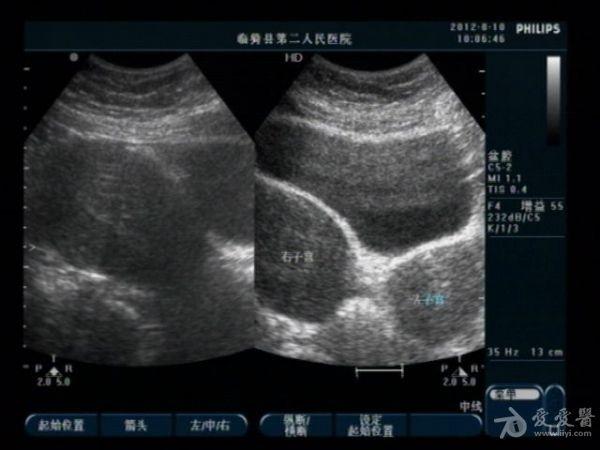

典型双子宫图像

前几天,我们科来了一位老病号,一年前剖腹产患者。当时手术证实“双子宫”今天超声图像可见一大一小两个子宫,右侧较大拟诊“子宫内膜异位症”。患者有经期腹痛史。

患者今年29岁,现生有一孩,就是剖宫产那个孩子。具体是那个子宫患者也不清楚,因在外地做的手术我们未能得到准确资料。患者近几个月来有明显的痛经史